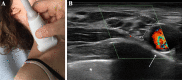

Axonal polyneuropathy is the main feature of hereditary transthyretin amyloidosis (ATTRv). Nerve morphological abnormalities have been reported, but longitudinal changes have never been assessed. We performed a prospective widespread nerve ultrasound evaluation and nerve cross-sectional area (CSA) was compared with baseline data in both ATTRv patients and pre-symptomatic carriers. Thirty-eight subjects were evaluated (mean follow-up 17.1 months), among them 21 had polyneuropathy while 17 were pre-symptomatic carriers. CSA significantly increased at brachial plexus in both groups (p = 0.008 and p = 0.012) pointing to progressive brachial plexus enlargement as a longitudinal biomarker of both disease progression and disease occurrence in pre-symptomatic carriers.